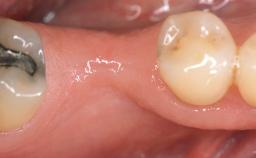

This case demonstrates that a connective-tissue graft in combination with a coronally positioned graft is an effective method of treating cases with peri-implant mucositis and an abutment-level sinus abscess. A 42-year-old man presented with a swelling adjacent to an implant crown at site 21. The swelling had been present for approximately three weeks and was constrained to the buccal and palatal gingival aspects of the implant. A discharge was noted on finger pressure, with localized gingival recession present on the mid- and distolabial aspects of the crown.